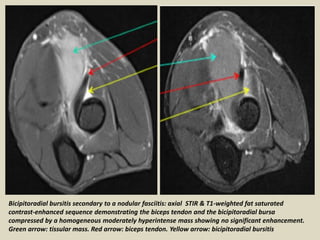

Bicipitoradial bursitis secondary to a nodular fasciitis: axial STIR & T1-weighted fat saturated

contrast-enhanced sequence demonstrating the biceps tendon and the bicipitoradial bursa

compressed by a homogeneous moderately hyperintense mass showing no significant enhancement.

Green arrow: tissular mass. Red arrow: biceps tendon. Yellow arrow: bicipitoradial bursitis